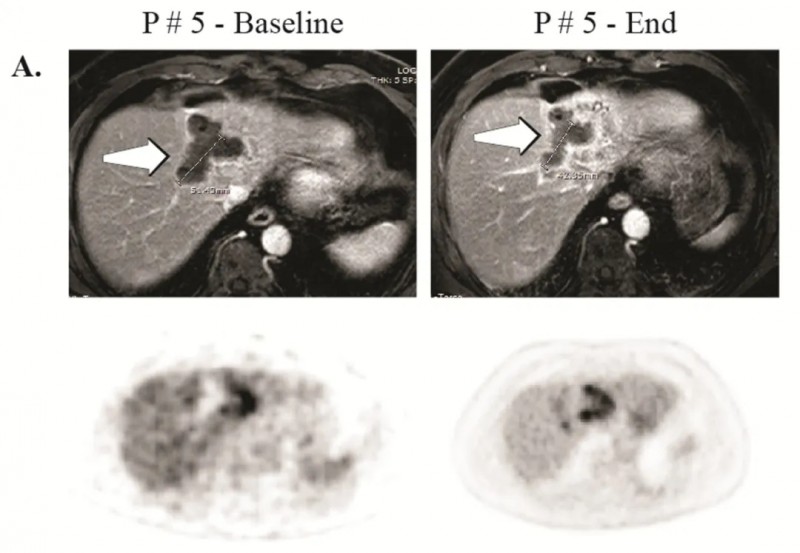

5号患者:在治疗后23个月(102周)仍存活且病情稳定,后续对残留肿瘤进行了微波消融(详见下图A)。

▲图源“Clin Cancer Res”,版权归原作者所有,如无意中侵犯了知识产权,请联系我们删除